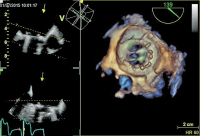

TEE

Abbildung 4: Deutliche Regression der Vegetationen nach 4-wöchiger Antibiose